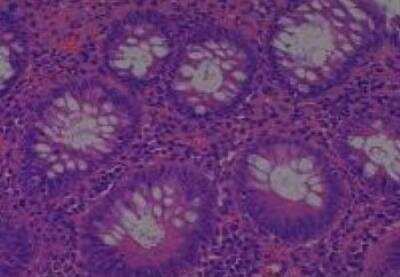

Scientific Data Images for Human Multi Tissue MicroArray (Normal Adjacent)

Hematoxylin & Eosin Stain: Human Common Tissue MicroArray (Normal Adjacent) [NBP2-30215] - 01. Stomach